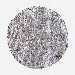

CERVICAL CANCER - Protein expressioni

A mouse-over function shows sample information and annotation data. Click on an image to view it in a full screen mode. Samples can be filtered based on level of antibody staining by selecting one or several of the following categories: high, medium, low and not detected. The assay and annotation is described here.

Note that samples used for immunohistochemistry by the Human Protein Atlas do not correspond to samples in the TCGA dataset.

Antibody stainingi

Antibody staining in the annotated cell types in the current human tissue is reported as not detected, low, medium, or high, based on conventional immunohistochemistry profiling in selected tissues. This score is based on the combination of the staining intensity and fraction of stained cells.

Each image is clickable and will lead to virtual microscopy that enables deeper exploration of all samples and also displays staining intensity scores, fraction scores and subcellular localization as well as patient and tissue information for each sample.

HPA022434

HPA022953

HPA022959

HPA028758

CAB007783

Staining

High

Medium

Low

Not detected

Intensity

Strong

Moderate

Weak

Negative

Quantity

>75%

75%-25%

<25%

None

Location

Nuclear

Cytoplasmic/membranous

Cytoplasmic/membranous,nuclear

Squamous cell carcinoma, NOS

Adenocarcinoma, NOS